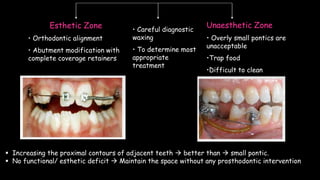

The document discusses pontic design for fixed dental prostheses. It covers pretreatment assessment of residual ridge contours, classifications of ridge deformities, surgical modification techniques, and ideal requirements for pontics. Pontic designs are classified based on their shape and materials. Factors in pontic selection include esthetics and oral hygiene. Common designs for anterior and posterior regions are described, including sanitary, ovate, and saddle pontics. Biological considerations for pontic design involve maintaining the residual ridge, abutment teeth, and supporting tissues.